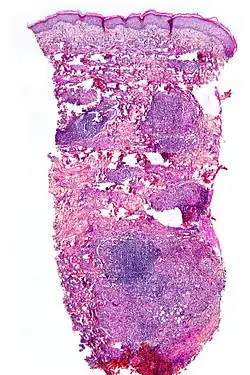

Histopathology

Although the exact cause of this condition is not known, it is an inflammatory disorder characterized by collagen degeneration, combined with a granulomatous response. It always involves the dermis diffusely, and sometimes also involves the deeper fat layer. Commonly, dermal blood vessels are thickened (Microangiopathy).[21]

NL is diagnosed by a skin biopsy, demonstrating superficial and deep perivascular and interstitial mixed inflammatory cell infiltrate (including lymphocytes, plasma cells, mononucleated and multinucleated histocytes, and eosinophils) in the dermis and subcutis, as well as necrotising vasculitis with adjacent necrobiosis and necrosis of adnexal structures.[23] Areas of necrobiosis are often more extensive and less well defined than in granuloma annulare. The presence of lipid in necrobiotic areas may be demonstrated by Sudan stains. Cholesterol clefts, fibrin, and mucin may also be present in areas of necrobiosis. Depending on the severity of the necrobiosis, certain cell types may be more predominant. When a lesion is in its early stages, neutrophils may be present, whereas in later stages of development, lymphocytes and histiocytes may be predominant.[24]